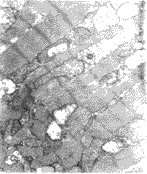

Effects of TP on myocardial ultra structure in rats after repeated +10 Gz stress As compared with the control (Fig.1),a significant myocardial ultrastructural injury was observed after repeated +10 Gz stress (Fig.2, Fig.3), whereas TP had significant protective effect on the cellular structural injury (Fig.4).

Fig.1 Normal myocardial cells of rat (longitudinal section of muscle segment). Z lines, M lines, a lot of mitochondria, glycogen granules and nuclei were shown(×10000×0.5)

Fig.2 Myocardial fibers were loose and breaking after repeated +10 Gz stress(×17000×0.5)

Fig.3 Myocardial mitochondria were heavily damaged after repeated +10Gz stress(×13000×0.5)

Fig.4 Compared with +10 Gz group, TP had significant protective effect on myocardial mitochondrial injury and maintainted muscle segment nearly normal (×10000×0.5)